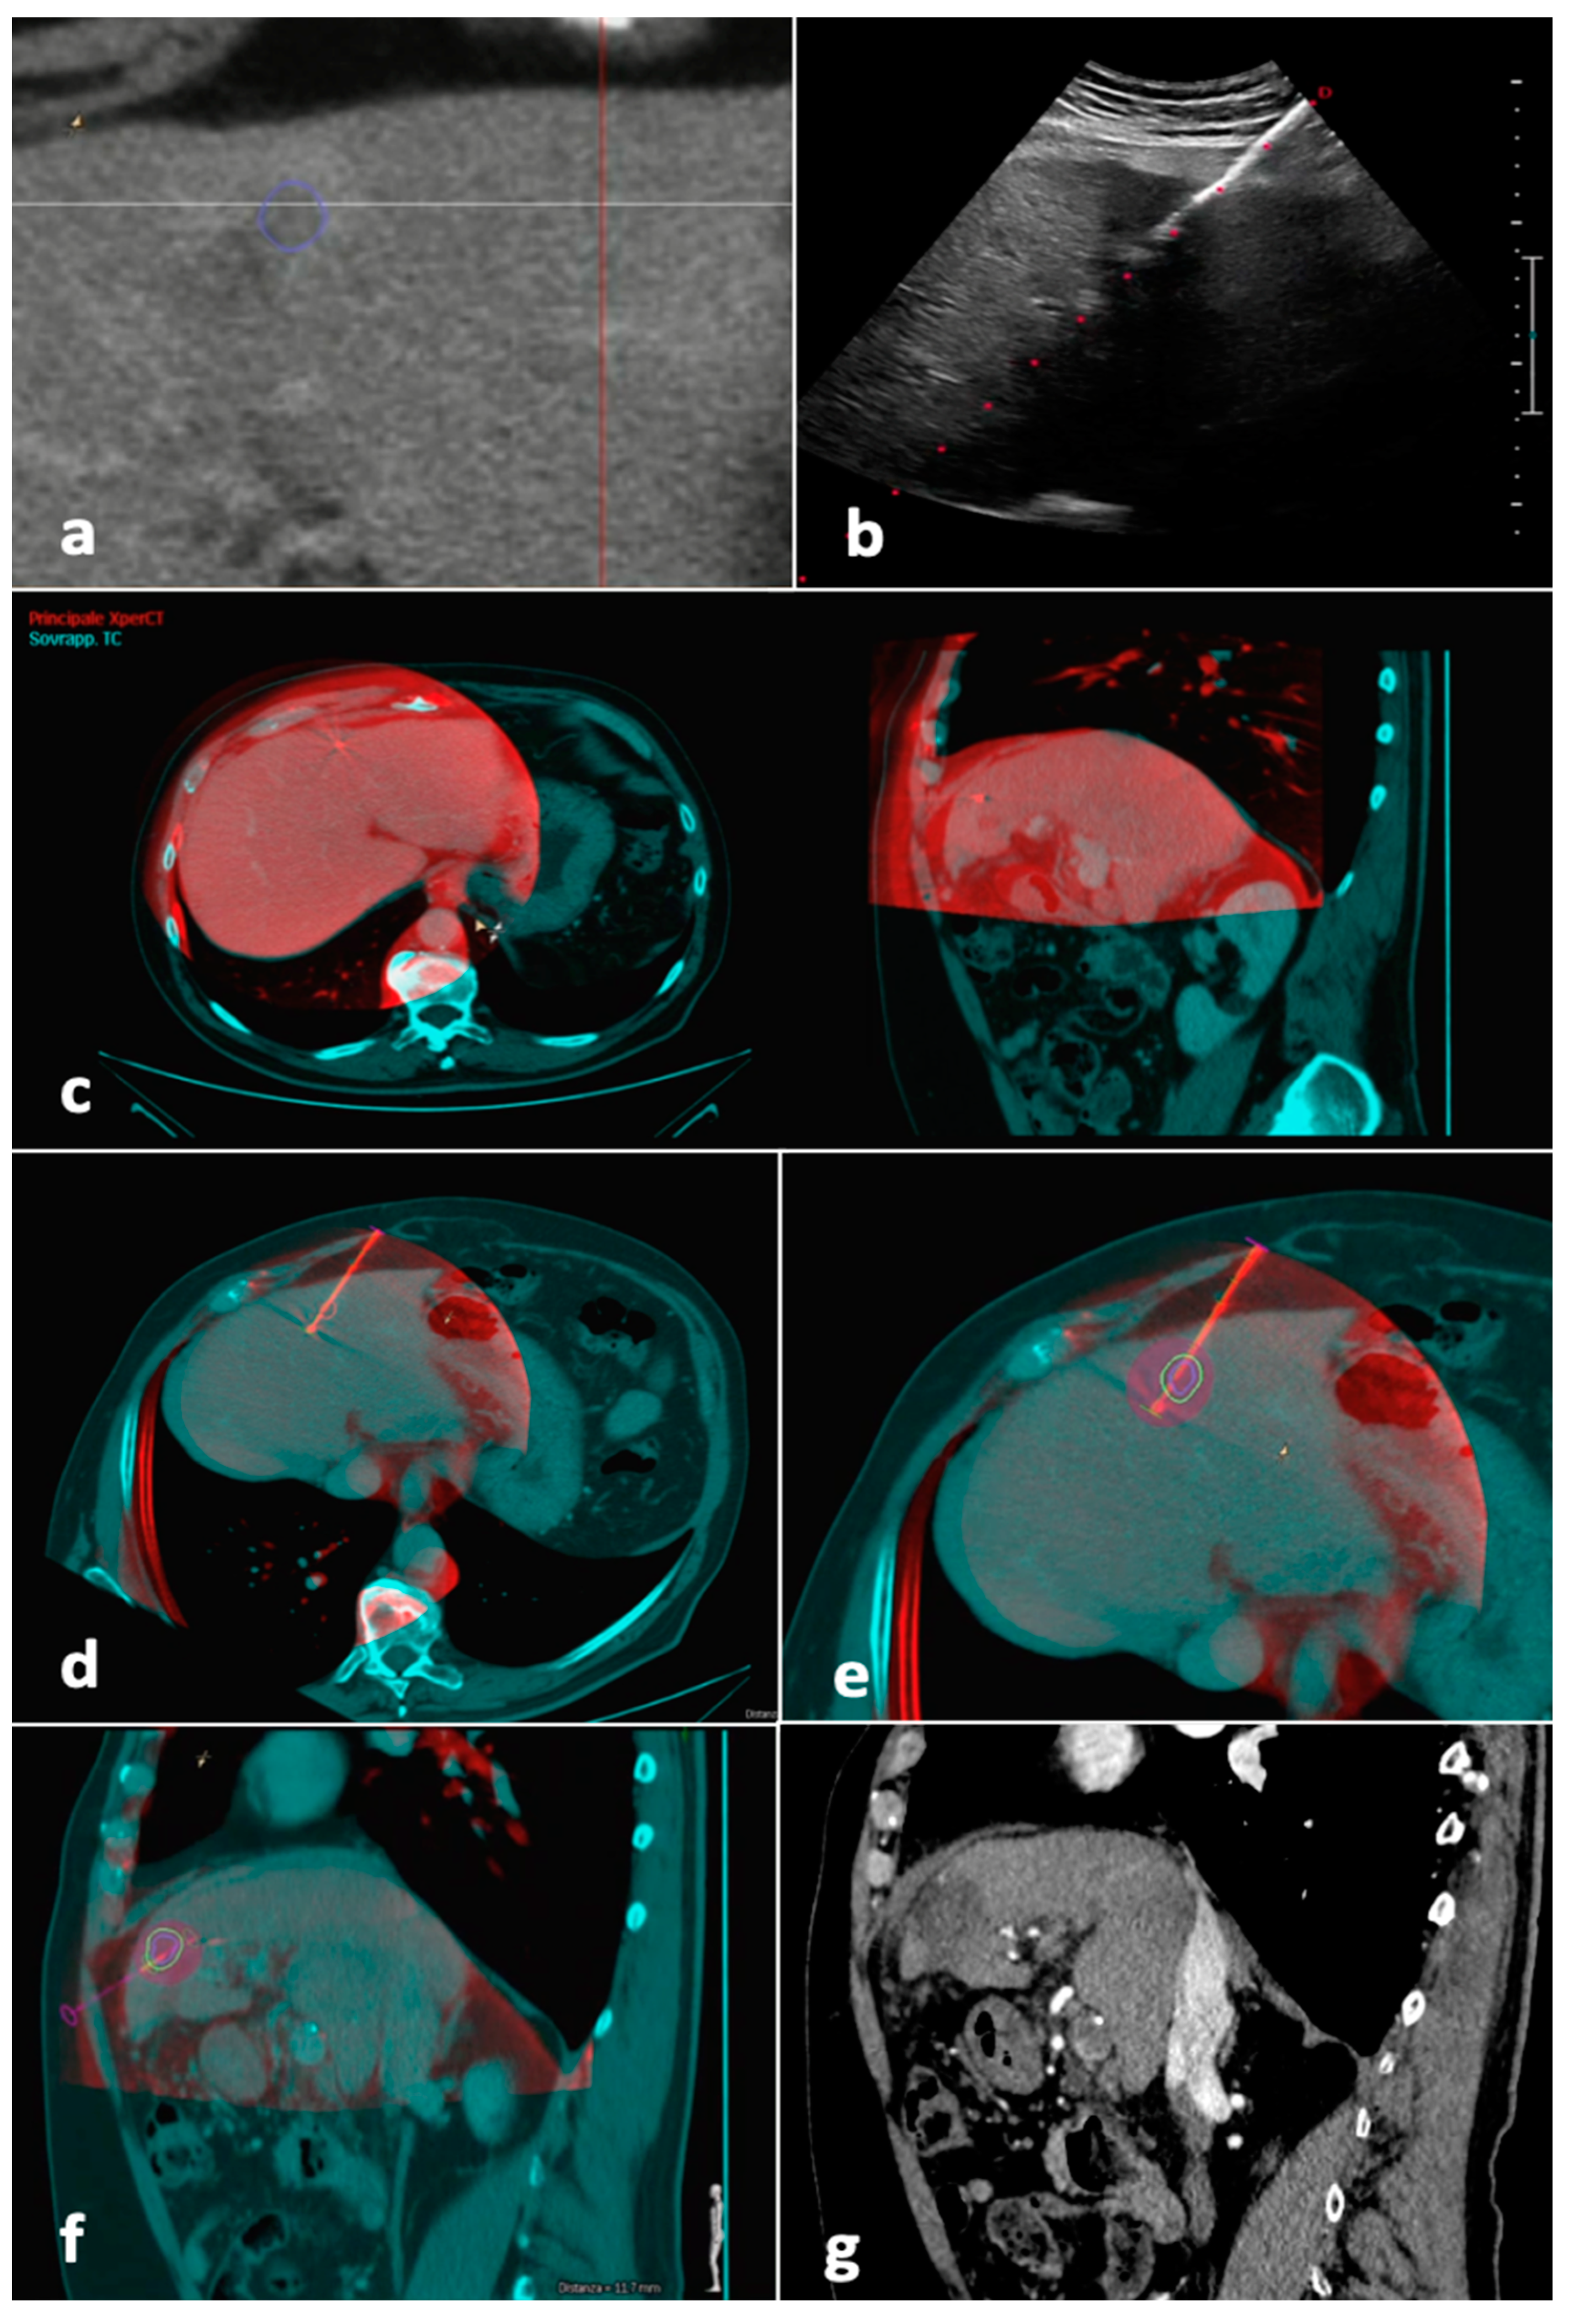

2.1. Procedure